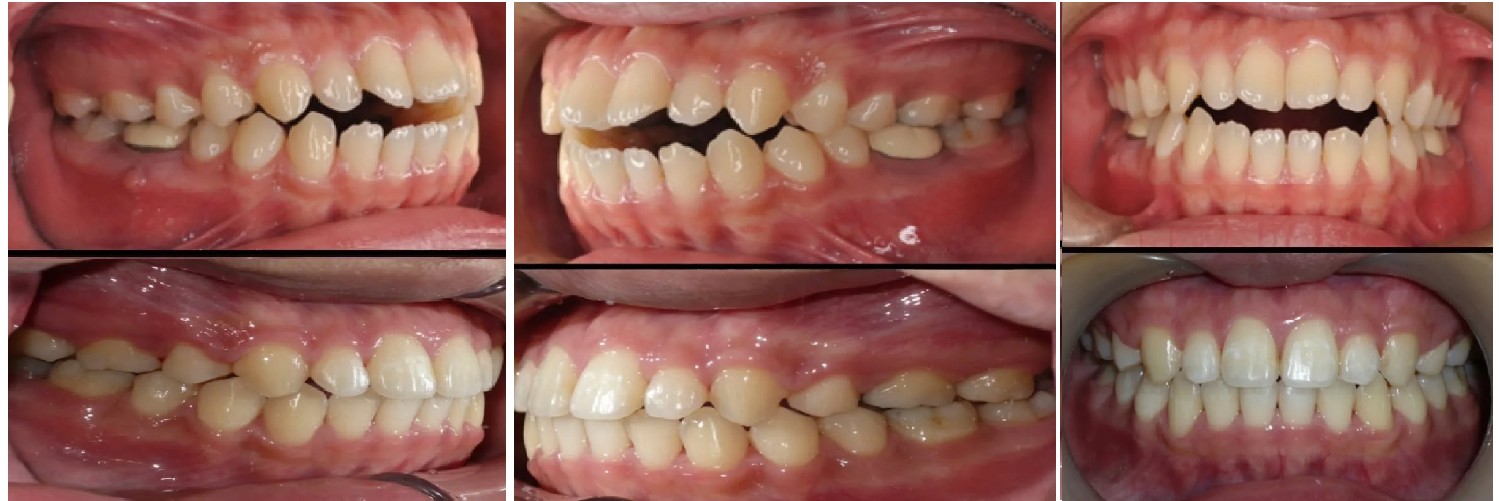

這位患者屬於開咬案例,治療前上下前牙無法咬合,經過矯正後恢復正常咬合,笑容也更自然。

F小姐曾是牙醫助理,了解許多咬合不正都可以利用矯正的方式處理,於是找矯正醫師諮詢,醫師初步評估前牙後牙皆有錯咬。

接下來做完矯正的資料收集、聽治療計劃並開始做矯正,以每3-4週回診的頻率,維持了幾年,終於在今年完成治療了,未來的日子也要配戴維持器,避免牙齒有變化。

矯正流程:矯正評估→資料收集→聽治療計劃→開始矯正→每3-4週回診調整→完成治療→配戴維持器

矯正是個漫長旅程,有許多食物(黏的、硬的、有嚼勁)是不能碰的,每餐都要刷牙(牙線、牙間刷),雖然過程很辛苦,但看到成果真的很開心。